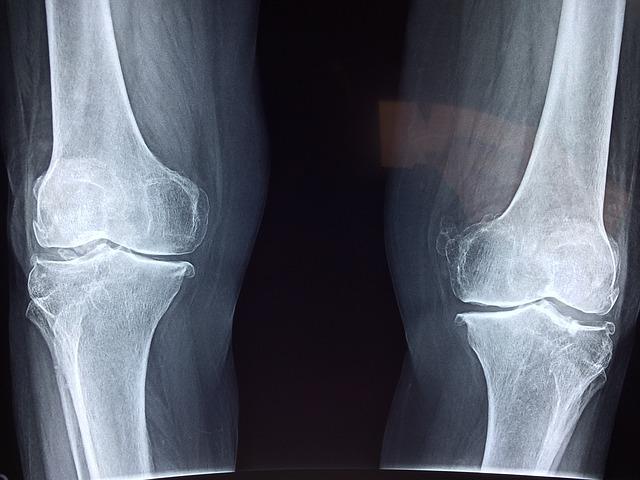

마가목에 포함된 프로보노이드 성분은 기관지에도 좋지만 관절염에도 좋습니다. 연골 손상을 보호하며 뼈의 파괴와 노화를 억제하는 효과가 있습니다.